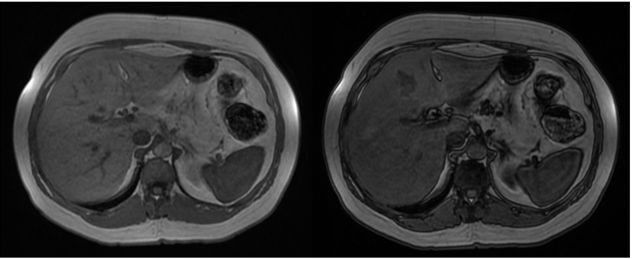

Mulher de 45 anos, sem história pessoal de câncer, foi submetida a exame de ressonância magnética do abdome superior com contraste venoso hepatoespecífico após achado de nódulo hepático incidental em ultrassonografia. Nas sequências pré-contraste, o nódulo apresentava discreto baixo sinal na ponderação T1 e discreto alto sinal na ponderação T2, ambas com supressão de gordura. Abaixo temos imagens nas sequências T1 em fase, T1 fora de fase, T1 pós-contraste (fase arterial) e T1 pós-contraste (fase hepatobiliar). As sequências pós-contraste mostram que o nódulo apresenta intenso realce arterial e hipossinal em relação ao parênquima na fase hepatobiliar.

I. Há queda de sinal na ponderação T1 fora de fase tanto no parênquima hepático como no nódulo do segmento IV hepático em relação à ponderação T1 em fase, sugerindo quantidade significativa de gordura intracelular no parênquima e no nódulo.

III. O nódulo do segmento IV hepático tem características compatíveis com adenoma esteatótico.